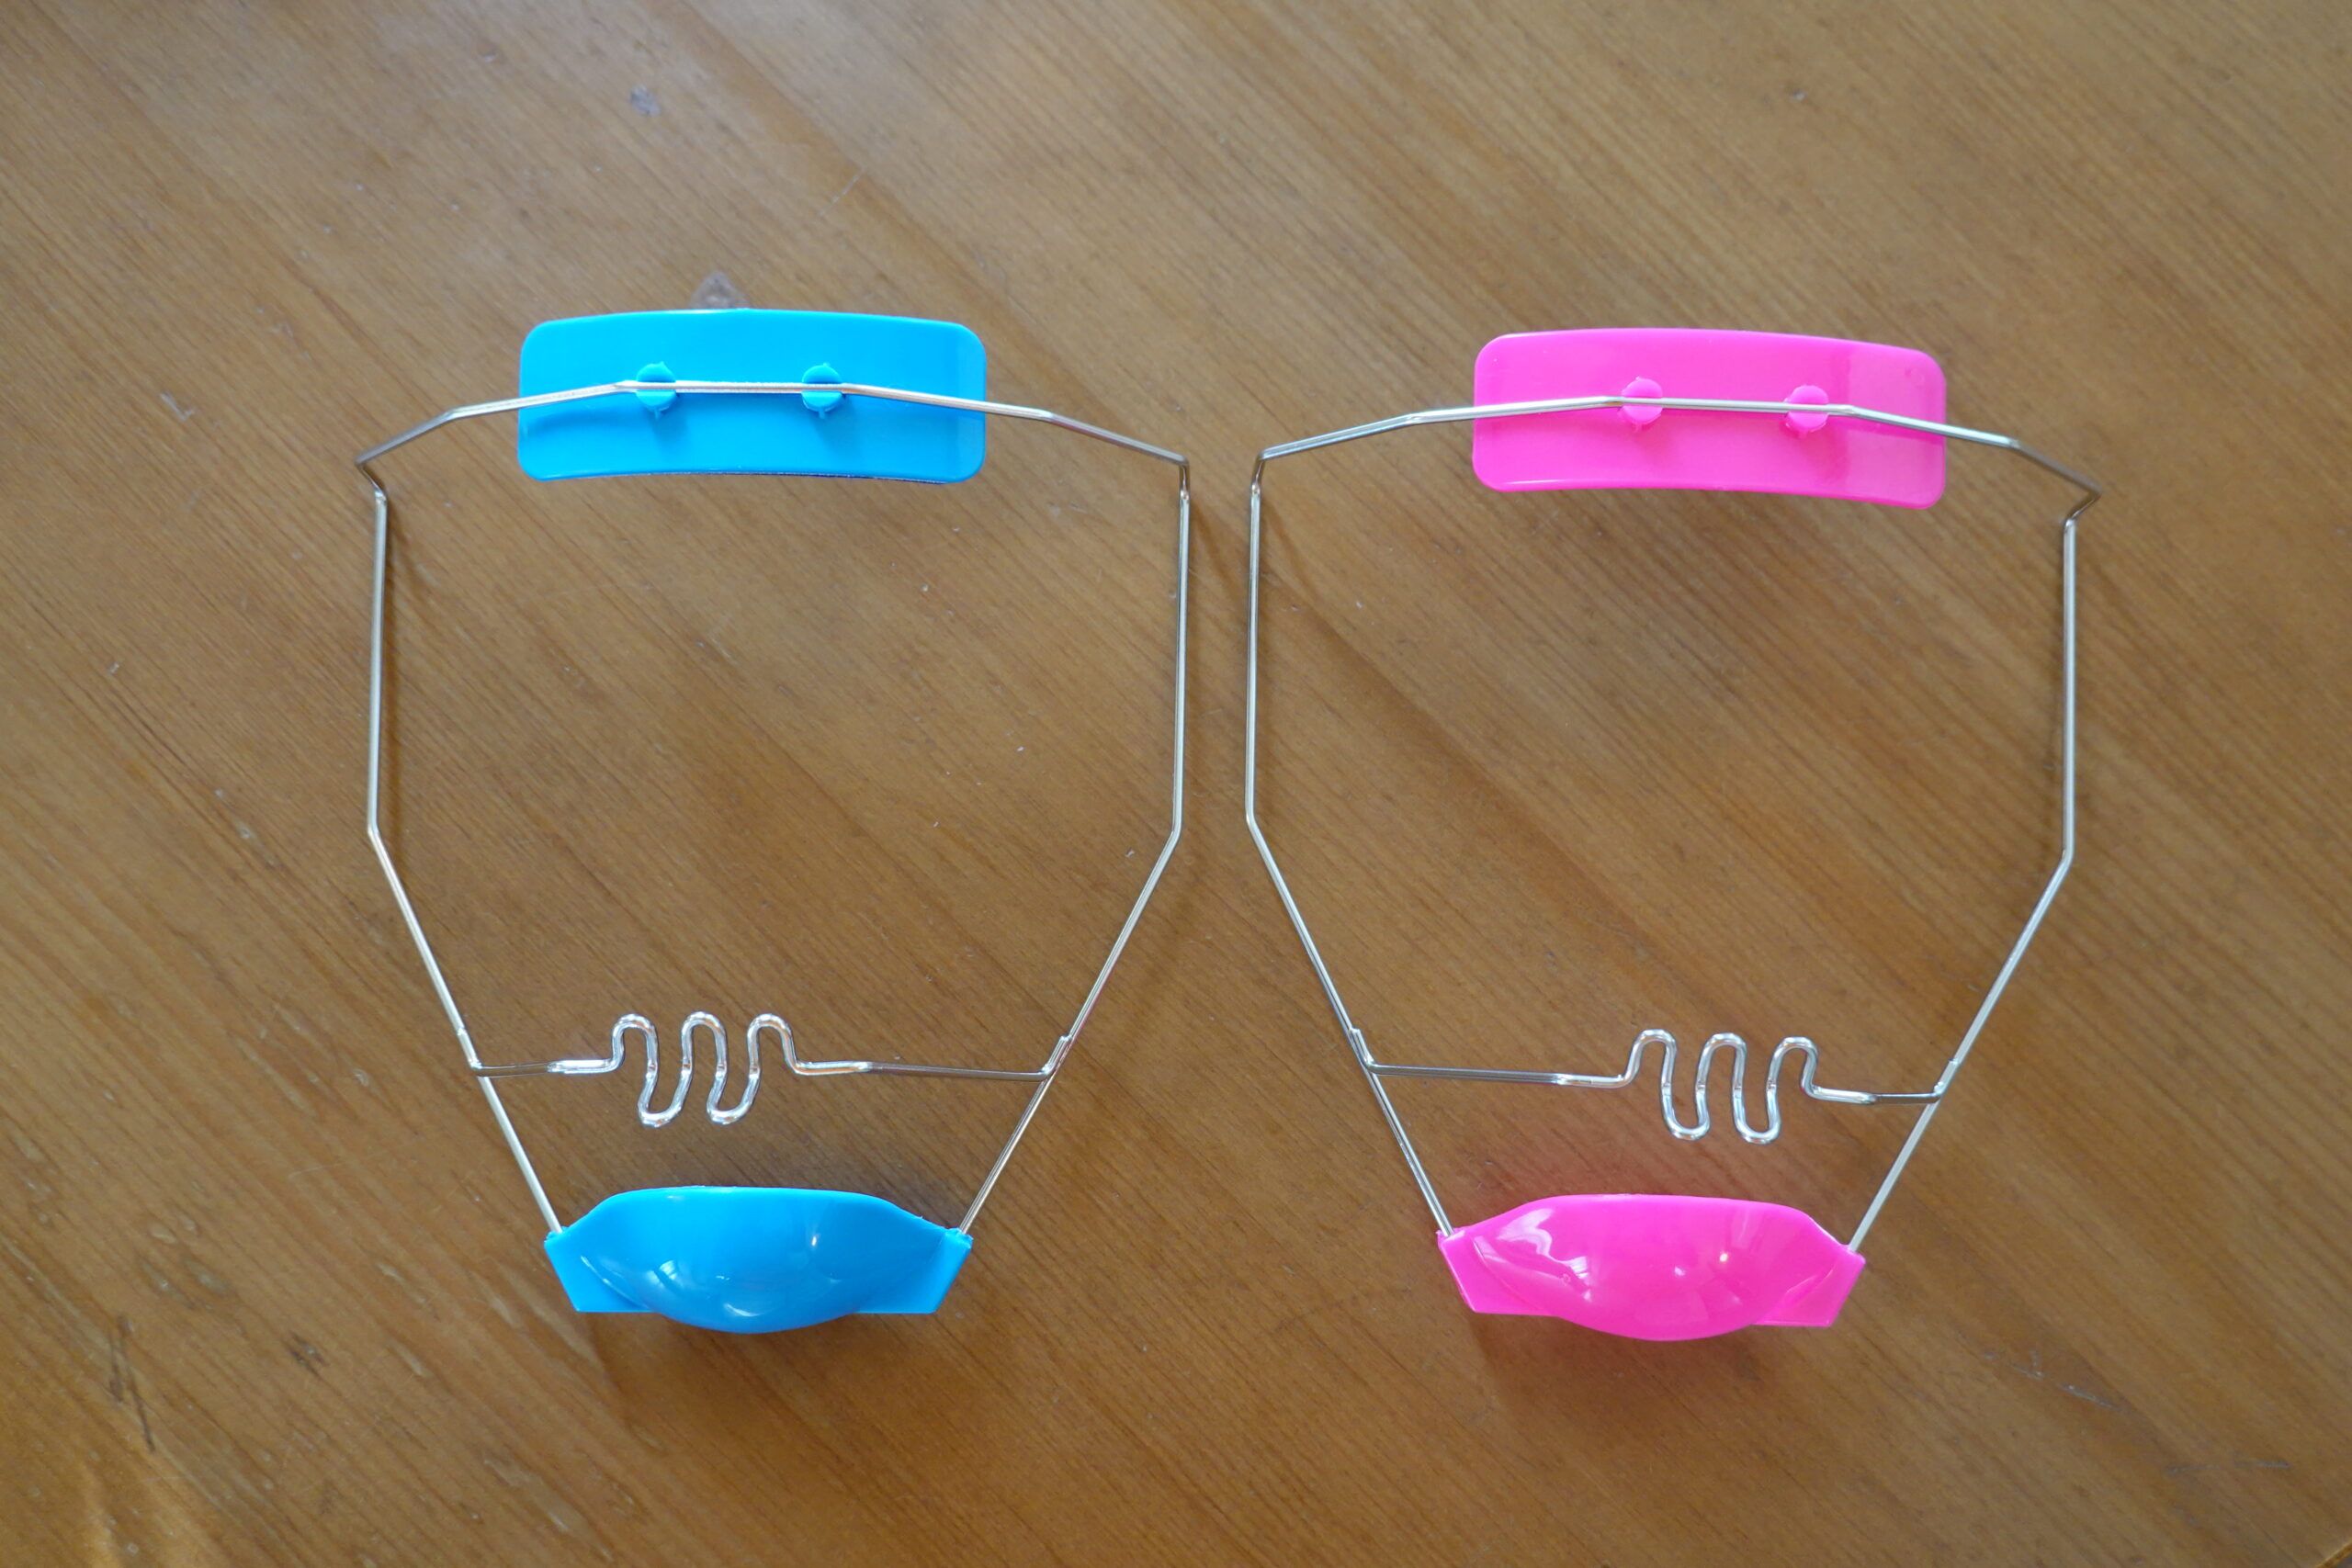

【編集者】小児矯正などで使われる「既製品のシールド状マウスピース」と、これまでの連載で伺った「インビザライン」にはどういった違いがあるのでしょうか?

【塩濱先生】一口にマウスピースと言っても、「既製品のシールド状マウスピース」と「個々の歯を動かすための完全オーダーメイドのマウスピース(インビザライン)」は、形状も用途も全く異なります。既製品のシールド状マウスピースは、いくつかのサイズが用意されていますが、子ども一人ひとりの口に合わせて作られているわけではありません。そのため子どもは装着を嫌がったり、すぐに外してしまったりします。受け口の原因が、唇の圧が強いことや舌が正しい位置にないことにある場合は、既製品のシールド状マウスピースがお口周りの筋機能に働きかけ、功を奏することもありますが、着けていられないと効果は期待できません。

■既製品のシールド状マウスピース

■既製品のシールド状マウスピース

また下顎の成長方向が前下方に強い場合は、前歯が合わさらない開咬状態を作ってしまうこともあります。歯は良い方向にも悪い方向にも動きます。一般歯科で簡単にできる矯正は、歯の傾きだけの受け口には功を奏することもありますが、顎のズレを検査しないで行われる治療は、高いリスクを伴っていることもご理解いただきたいです。

インビザラインは歯の傾きや位置が原因で受け口が生じている場合に効果的ですが、残念ながらこちらにも骨格的な問題の解決は期待できません。そのため当院では、まず顎外装置(お口の外で使用する装置)を使って上下の顎関係の改善を優先し、その後の仕上げで前歯を綺麗に並べるためにインビザラインを用いることが多いです。顎外装置を使わないと、上顎の成長促進は行えません。

■当院(お口の外で使用する装置)は、頭から被せる大掛かりなものではなく、違和感も少ない。男の子と女の子で色を使い分けている。

■当院(お口の外で使用する装置)は、頭から被せる大掛かりなものではなく、違和感も少ない。男の子と女の子で色を使い分けている。